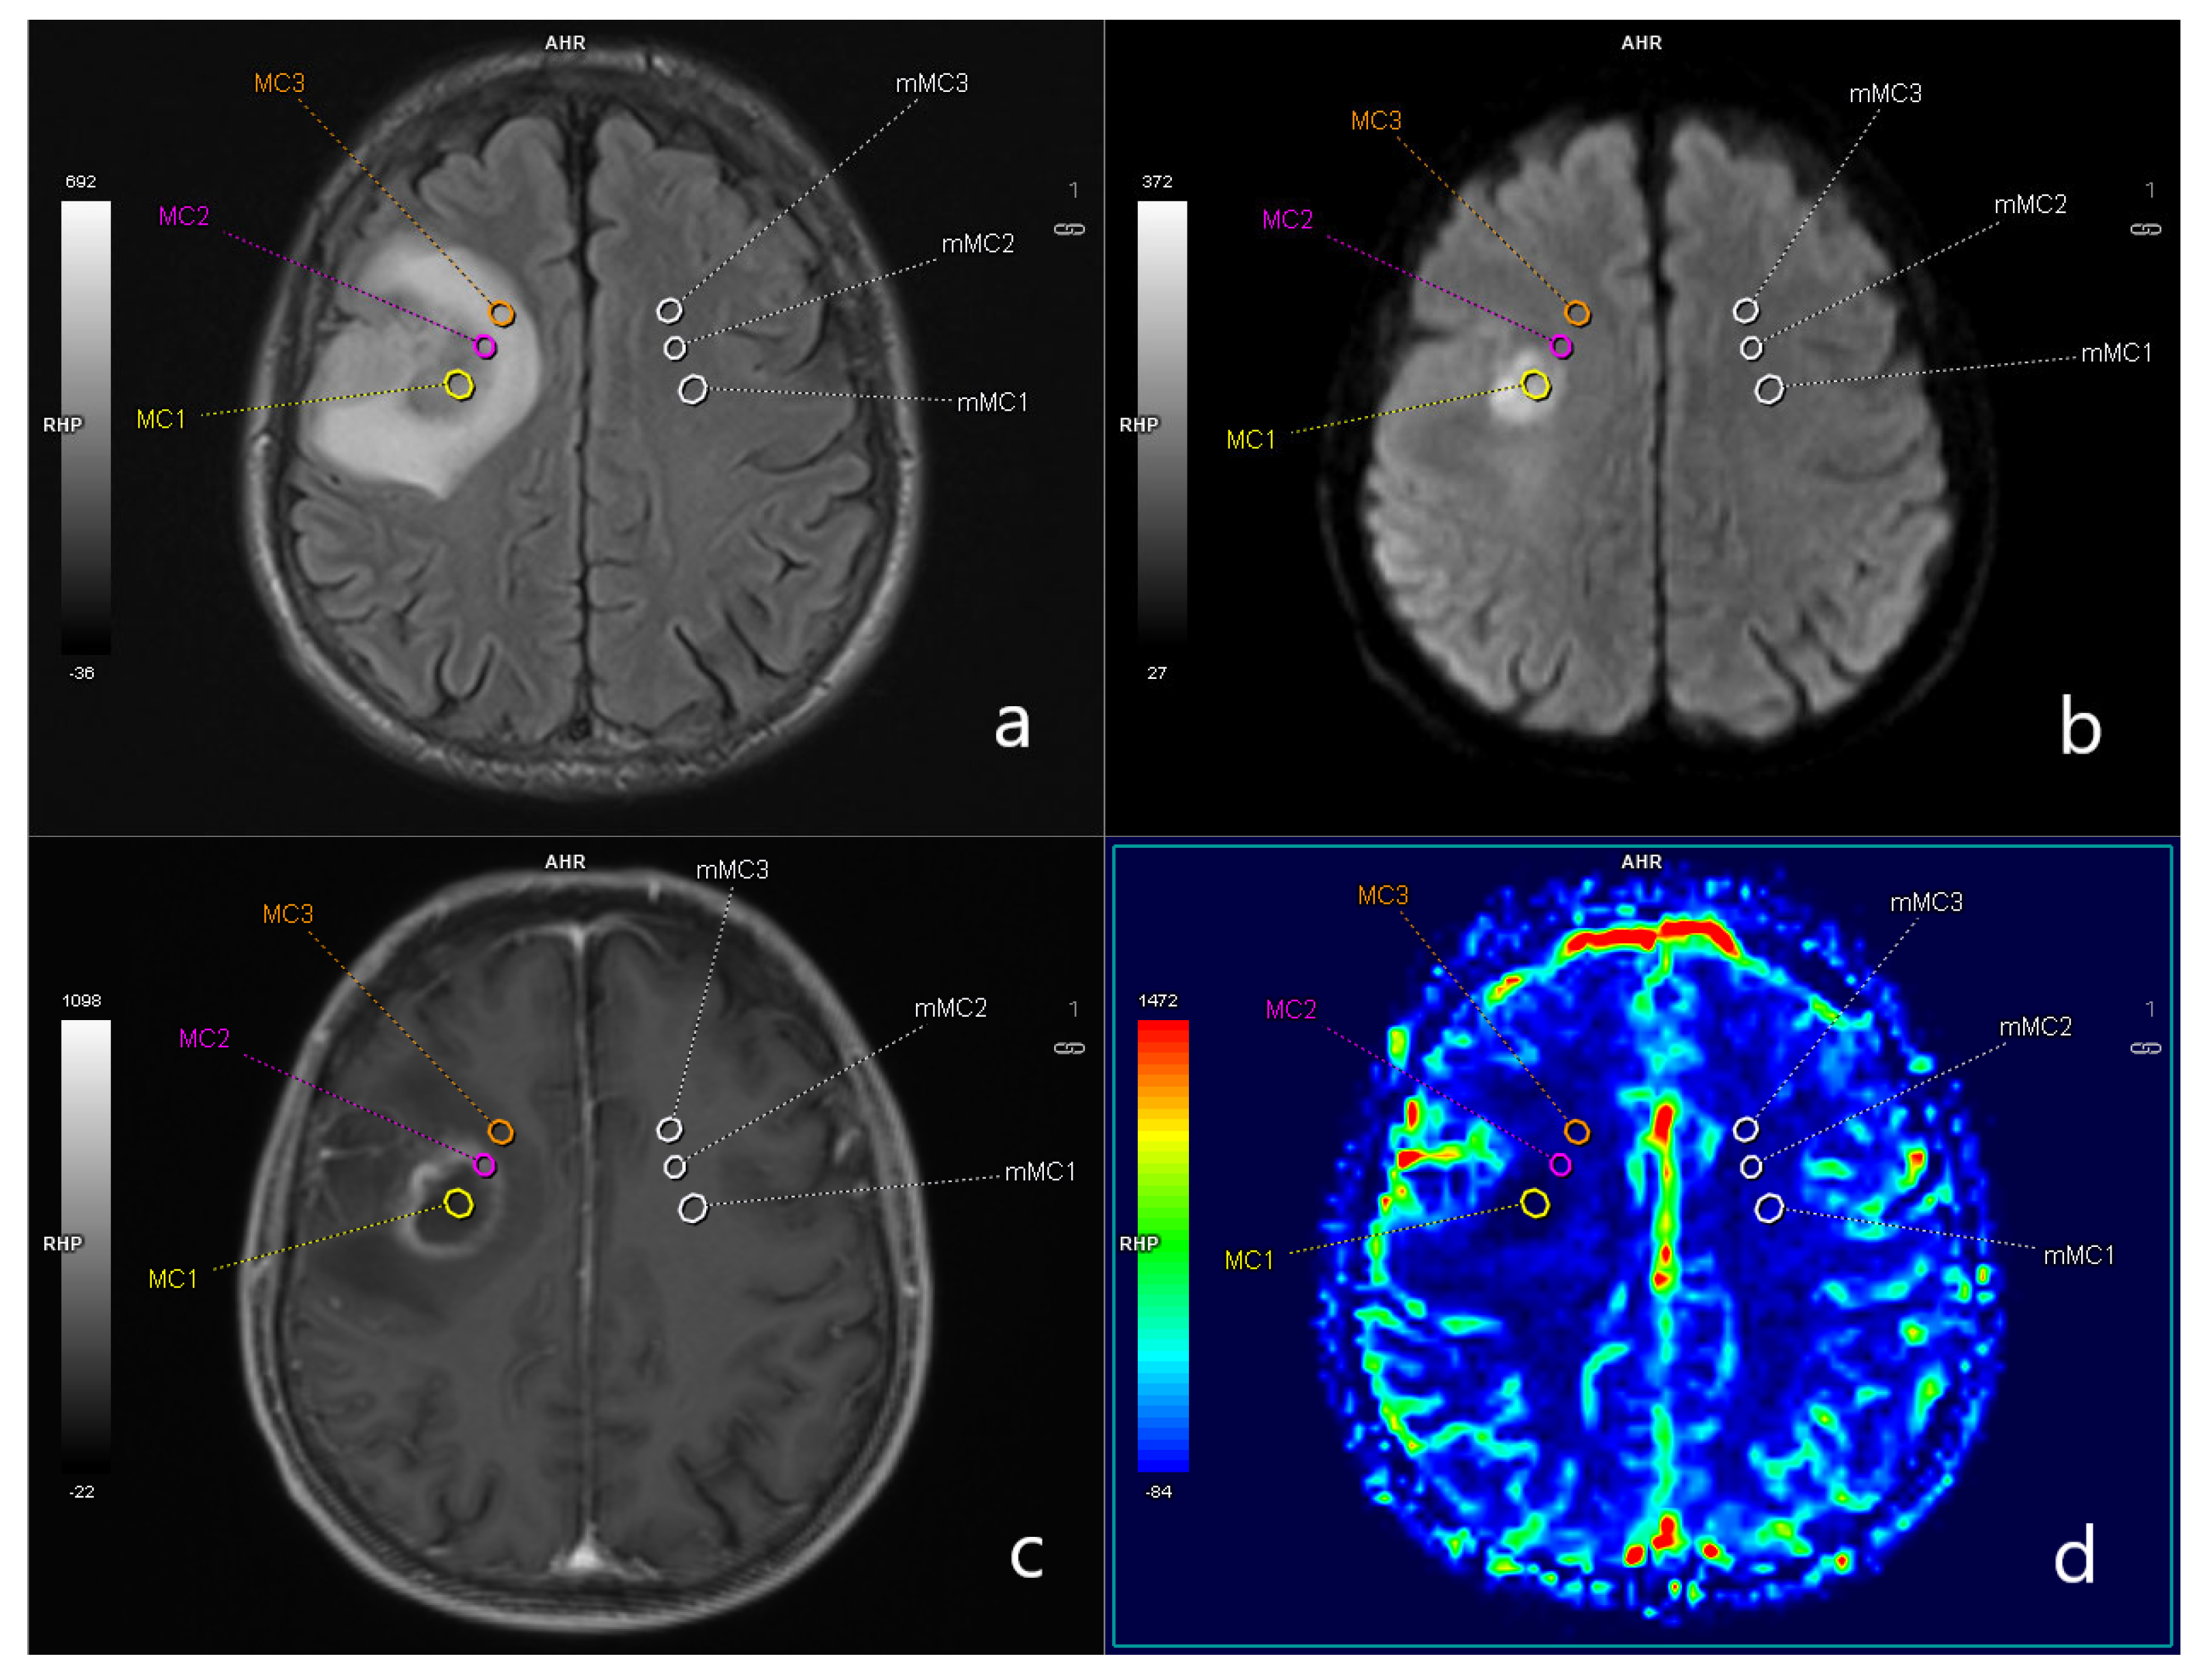

2.2. Imaging

2.3. Postprocessing